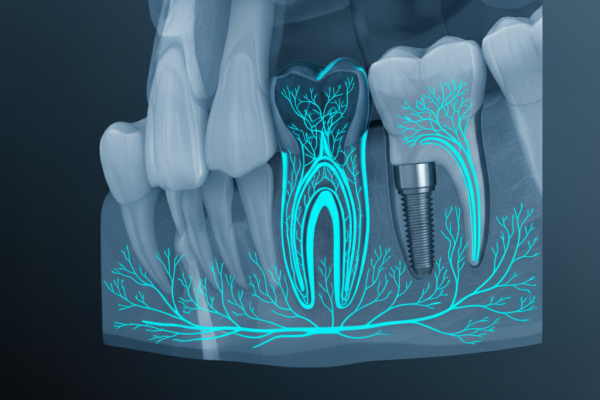

A tomografia de feixe cônico (Cone Beam) oferece imagens tridimensionais detalhadas, essenciais para diagnósticos precisos.

A impressão 3D na odontologia permite a criação de modelos, próteses e guias cirúrgicos personalizados com alta precisão